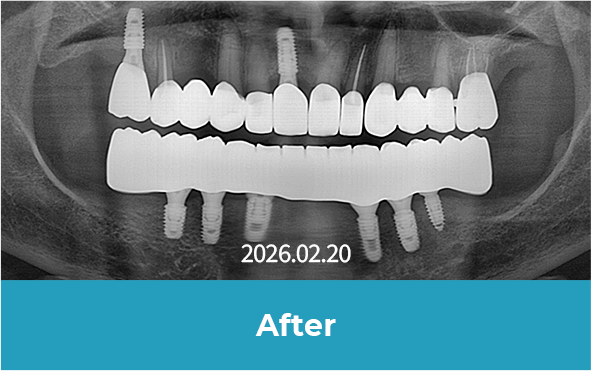

All-on-x는 4~6개의 임플란트만으로

전체 치아를 지지하는 방식으로 진행됩니다.

기존 전체 임플란트 대비 식립 개수를 줄이면서도

안정적인 지지력을 확보할 수 있어

틀니의 불편함 없이 자연스러운 저작이 가능합니다.

치료 후 사진

[ 환자분의 동의서 작성 후 게시하였습니다 ]